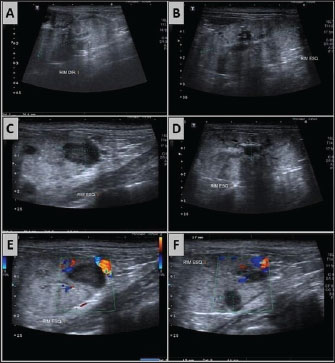

With the administration of meropenem according to the antibiotic susceptibility profile, normalization of the leukogram was observed (Table 1). Renal abscesses, visualized via abdominal ultrasonography (Fig. 2), regressed, leading to urosepsis control. The uremic crisis was resolved. On the 14th day of hospitalization, the patient was discharged for continued treatment at home for the hepatopathy that developed during the infection. The clinical management of CKD was maintained.

Fig. 2. Ultrasound images of the right and left kidneys following treatment with meropenem (8.5 mg/kg SC twice daily for 10 days) in a canine patient with Klebsiella infection. (A–D) Both kidneys show a loss of corticomedullary distinction and definition. (A–C) In the left kidney, there was noticeable remission of the hypoechoic nodular structures, which were previously identified as consistent with renal abscesses.

This case report describes the development of urosepsis and renal abscesses caused by multidrug-resistant Klebsiella infection in a dog and highlights the importance of urine culture and antimicrobial susceptibility testing in guiding the selection of the most appropriate antibiotic for effective infection control. The therapeutic approach used for purulent renal collections demonstrates that antibiotic therapy alone, rather than percutaneous drainage and/or surgical methods, can be effective in resolving renal cortical abscesses measuring approximately 4–5 cm in dogs. This approach avoided the use of invasive therapeutic methods that could contribute to further renal parenchymal injury. Moreover, the regression of the lesions, confirmed by ultrasonographic follow-up, underscores the essential role of imaging in monitoring the response to conservative therapy without percutaneous drainage and in excluding differential diagnoses such as neoplasia.

The hypoechoic structures identified in the left kidney did not require percutaneous drainage, suggesting the possibility of renal abscess remission with pharmacological intervention alone (Dalla Palma et al., 1999; Lee et al., 2010). Previous reports failed to successfully treat dogs using antibiotic therapy alone (Cola et al., 2020; Rohini et al., 2021; Véran et al., 2021). The decision to opt for pharmacological treatment over percutaneous drainage or surgical methods was based on previous studies by Dalla Palma et al. (1999) and Lee et al. (2010), which reported involution of renal and perirenal abscesses up to 5 cm in diameter with antimicrobial therapy alone in humans. In addition, the patient already exhibited renal parenchymal function instability, which contributed to the selection of therapeutic alternatives that would not worsen the existing renal injury. The remission of these structures on ultrasonography after antibiotic treatment supports the hypothesis that these purulent collections were present in the renal parenchyma, ruling out neoplasms as a differential diagnosis.